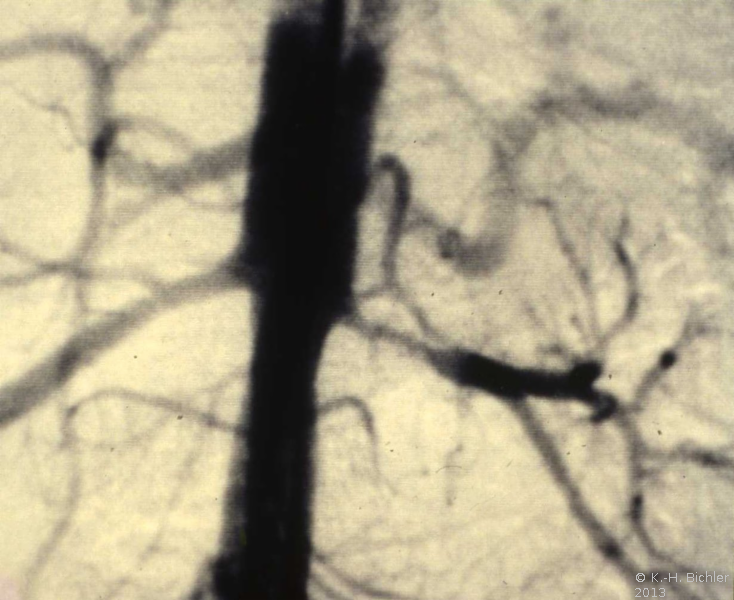

Die Röntgenübersicht der Niere und ableitenden Harnwege zeigten keinen Anhalt für Konkrement. Im Ausscheidungsurogramm eine "stumme Niere" links (Abbildung 19a). Bei der retrograden Sondierung links fand sich keine Abflussbehinderung (Stein oder Stenose) (Abbildung 19c). Im MCU kein Anhalt für Reflux (Abbildung 19b). Im Nierenfunktionsszintigramm MAG3 wurde eine seitengetrennte Funktionsverteilung von rechts zu links wie 93% zu 7% festgestellt. Zur Abklärung eventueller Gefäßalterationen erfolgte eine Renovasographie mit dem Nachweis einer langstreckigen Stenose der linken Arteria renalis (Abbildung 19d). Wegen des Verdachtes auf eine generalisierte Arteriitis wurden Angiographien weiterer Gefäßgebiete durchgeführt: Dabei fanden sich eine geringgradige Einengung der infrarenalen Aorta und der linken Arteria subclavia.